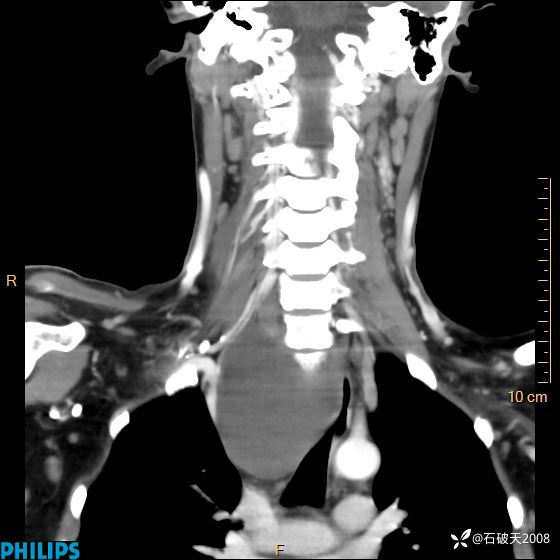

平扫

冠状位